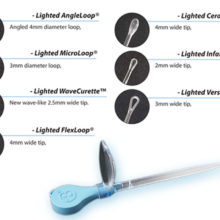

Texa Biomedicali seleziona i migliori prodotti nell’ambito del Monouso per Otorinolaringoiatra (ORL). Alta affidabilità e standard qualitativi in relazione alla vendita di Kit ORL sterili, curettes ORL, speculum monouso.